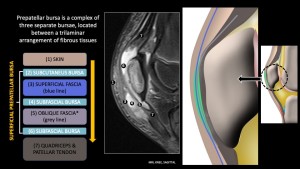

Superficial bursitis:The prepatellar and superficial infrapatellar bursae are the main superficial bursae of the anterior knee. The prepatellar bursa lies anterior to the patella and consists of three bursae between fibrous layers, while the superficial infrapatellar bursa is located anterior and slightly superior to the tibial tuberosity and is present in ~55% of specimens[4].